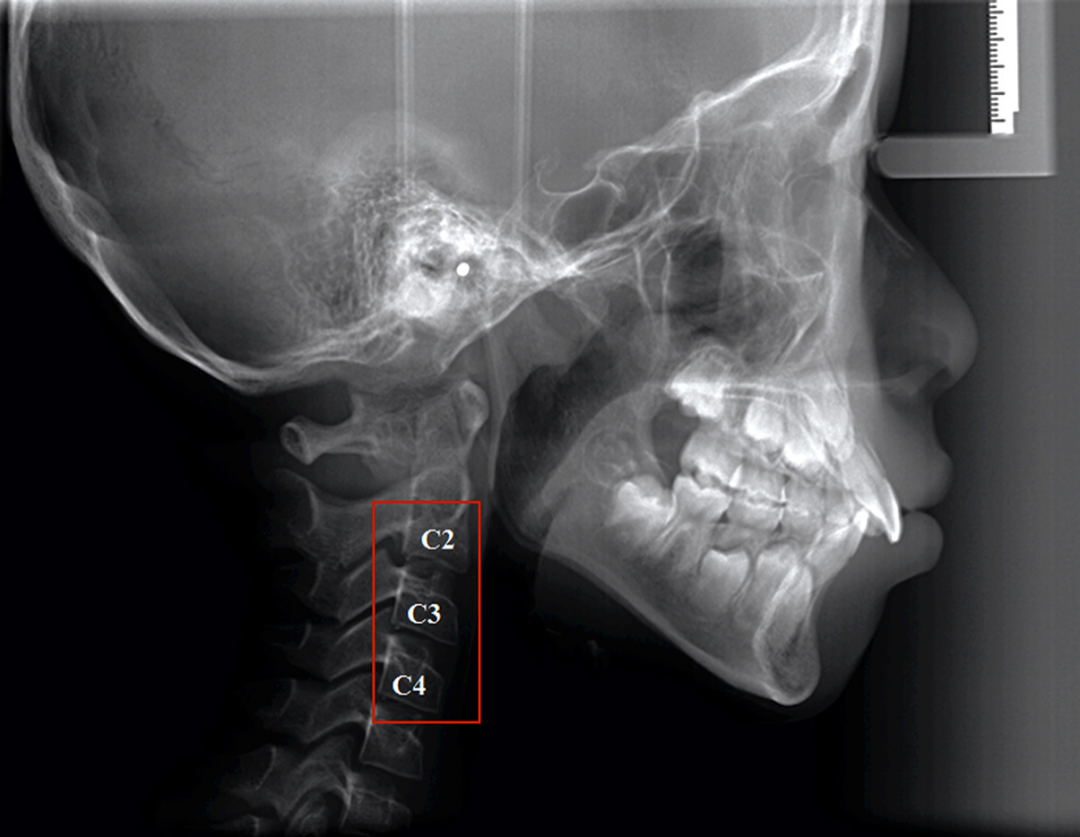

如果要看生长发育,其实我们在临床上,我们在给孩子拍头侧片子的时候,那个颈椎就是个最好的一个指征。

一般来讲在头侧片子上,我们能看到第一颈椎和第二颈椎是融合的,第三颈椎是关键点。

如果第三颈椎是扁平的,那说明距离生长发育高峰期,至少还有两年时间,如果它是正方形,说明到了生长发育的高峰期;如果是个矩形并且底部变弯了,说明就不长了,所以这三个形状是临床上一个鉴别的方式和方法。